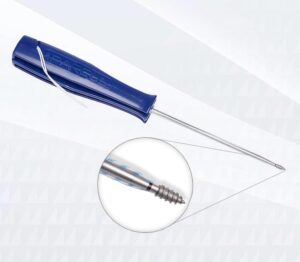

MiTi

Se recomiendan los anclajes de sutura de rosca MiTi para una variedad de aplicaciones en juntas pequeñas debido a su pequeño diámetro y su resistencia fiable a la retirada.